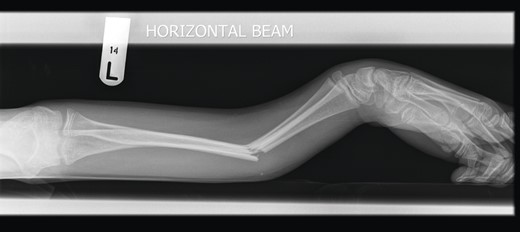

A 12-year-old male patient sustained a closed midshaft both-bone forearm fracture of their non-dominant arm from a fall on a trampoline (Figs 1 and 2). Anatomical reduction was achieved with a manipulation under anaesthesia (MUA), but it was noticed that there was a mechanical block to extension of the ring finger. The radius and ulna were therefore approached through separate incisions and it was discovered that the FDP was entrapped at the ulna fracture at the level of the musculotendinous junction. Following release the fingers regained a full range of motion and the patient went on to heal without further complication (Figs 3 and 4).

Pre-operative anteroposterior (AP) radiograph showing level of fracture at the junction of proximal two-thirds and distal one-third.